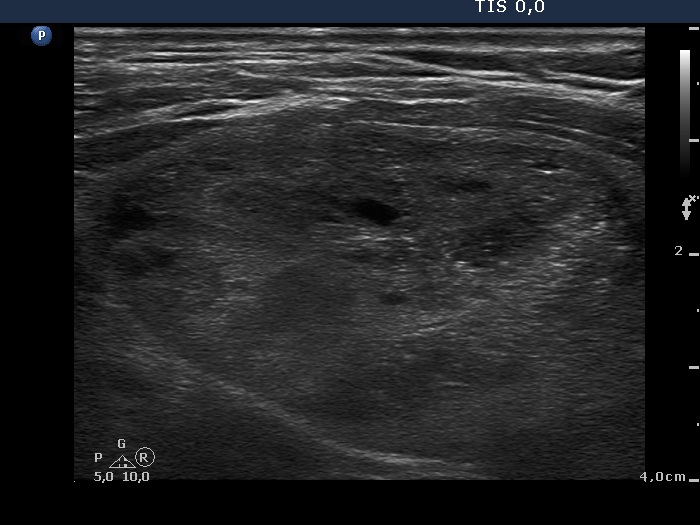

Ultrasonography. The right thyroid was intact. A large nodular area occupied almost the entire left thyroid. It was composed of moderately hypoechogenic, cystic, echonormal and hyperechogenic discrete lesions. The whole lesion was surrounded with an incomplete halo and presented a type 2 vascular pattern.

The sonographic pattern, i.e. a large nodular area composed of discrete lesions with different echogenicity is characteristic of a benign, hyperplastic nodule.